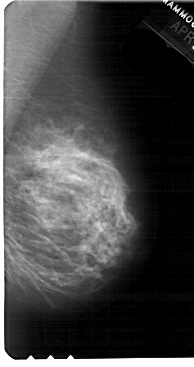

A_1766_1.RIGHT_CC